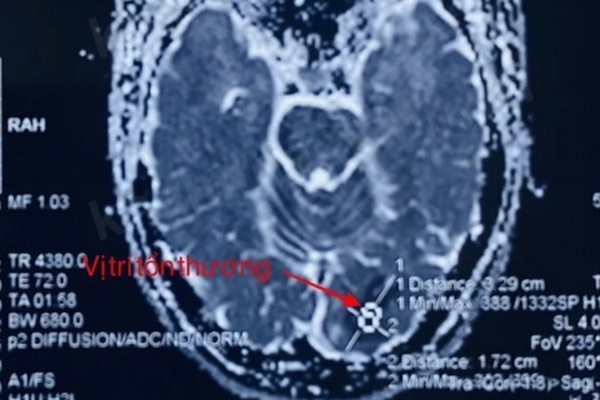

Người này được đưa vào bệnh viện trong tình trạng thị lực mắt phải 8/10, soi đáy mắt và mắt trái bình thường, kèm tê bì mặt và nửa người phải. Kết quả chụp cộng hưởng từ sọ não cho thấy hình ảnh nhồi máu não mới thuỳ chẩm bên trái.

Ảnh chụp tổn thương não của người bệnh.